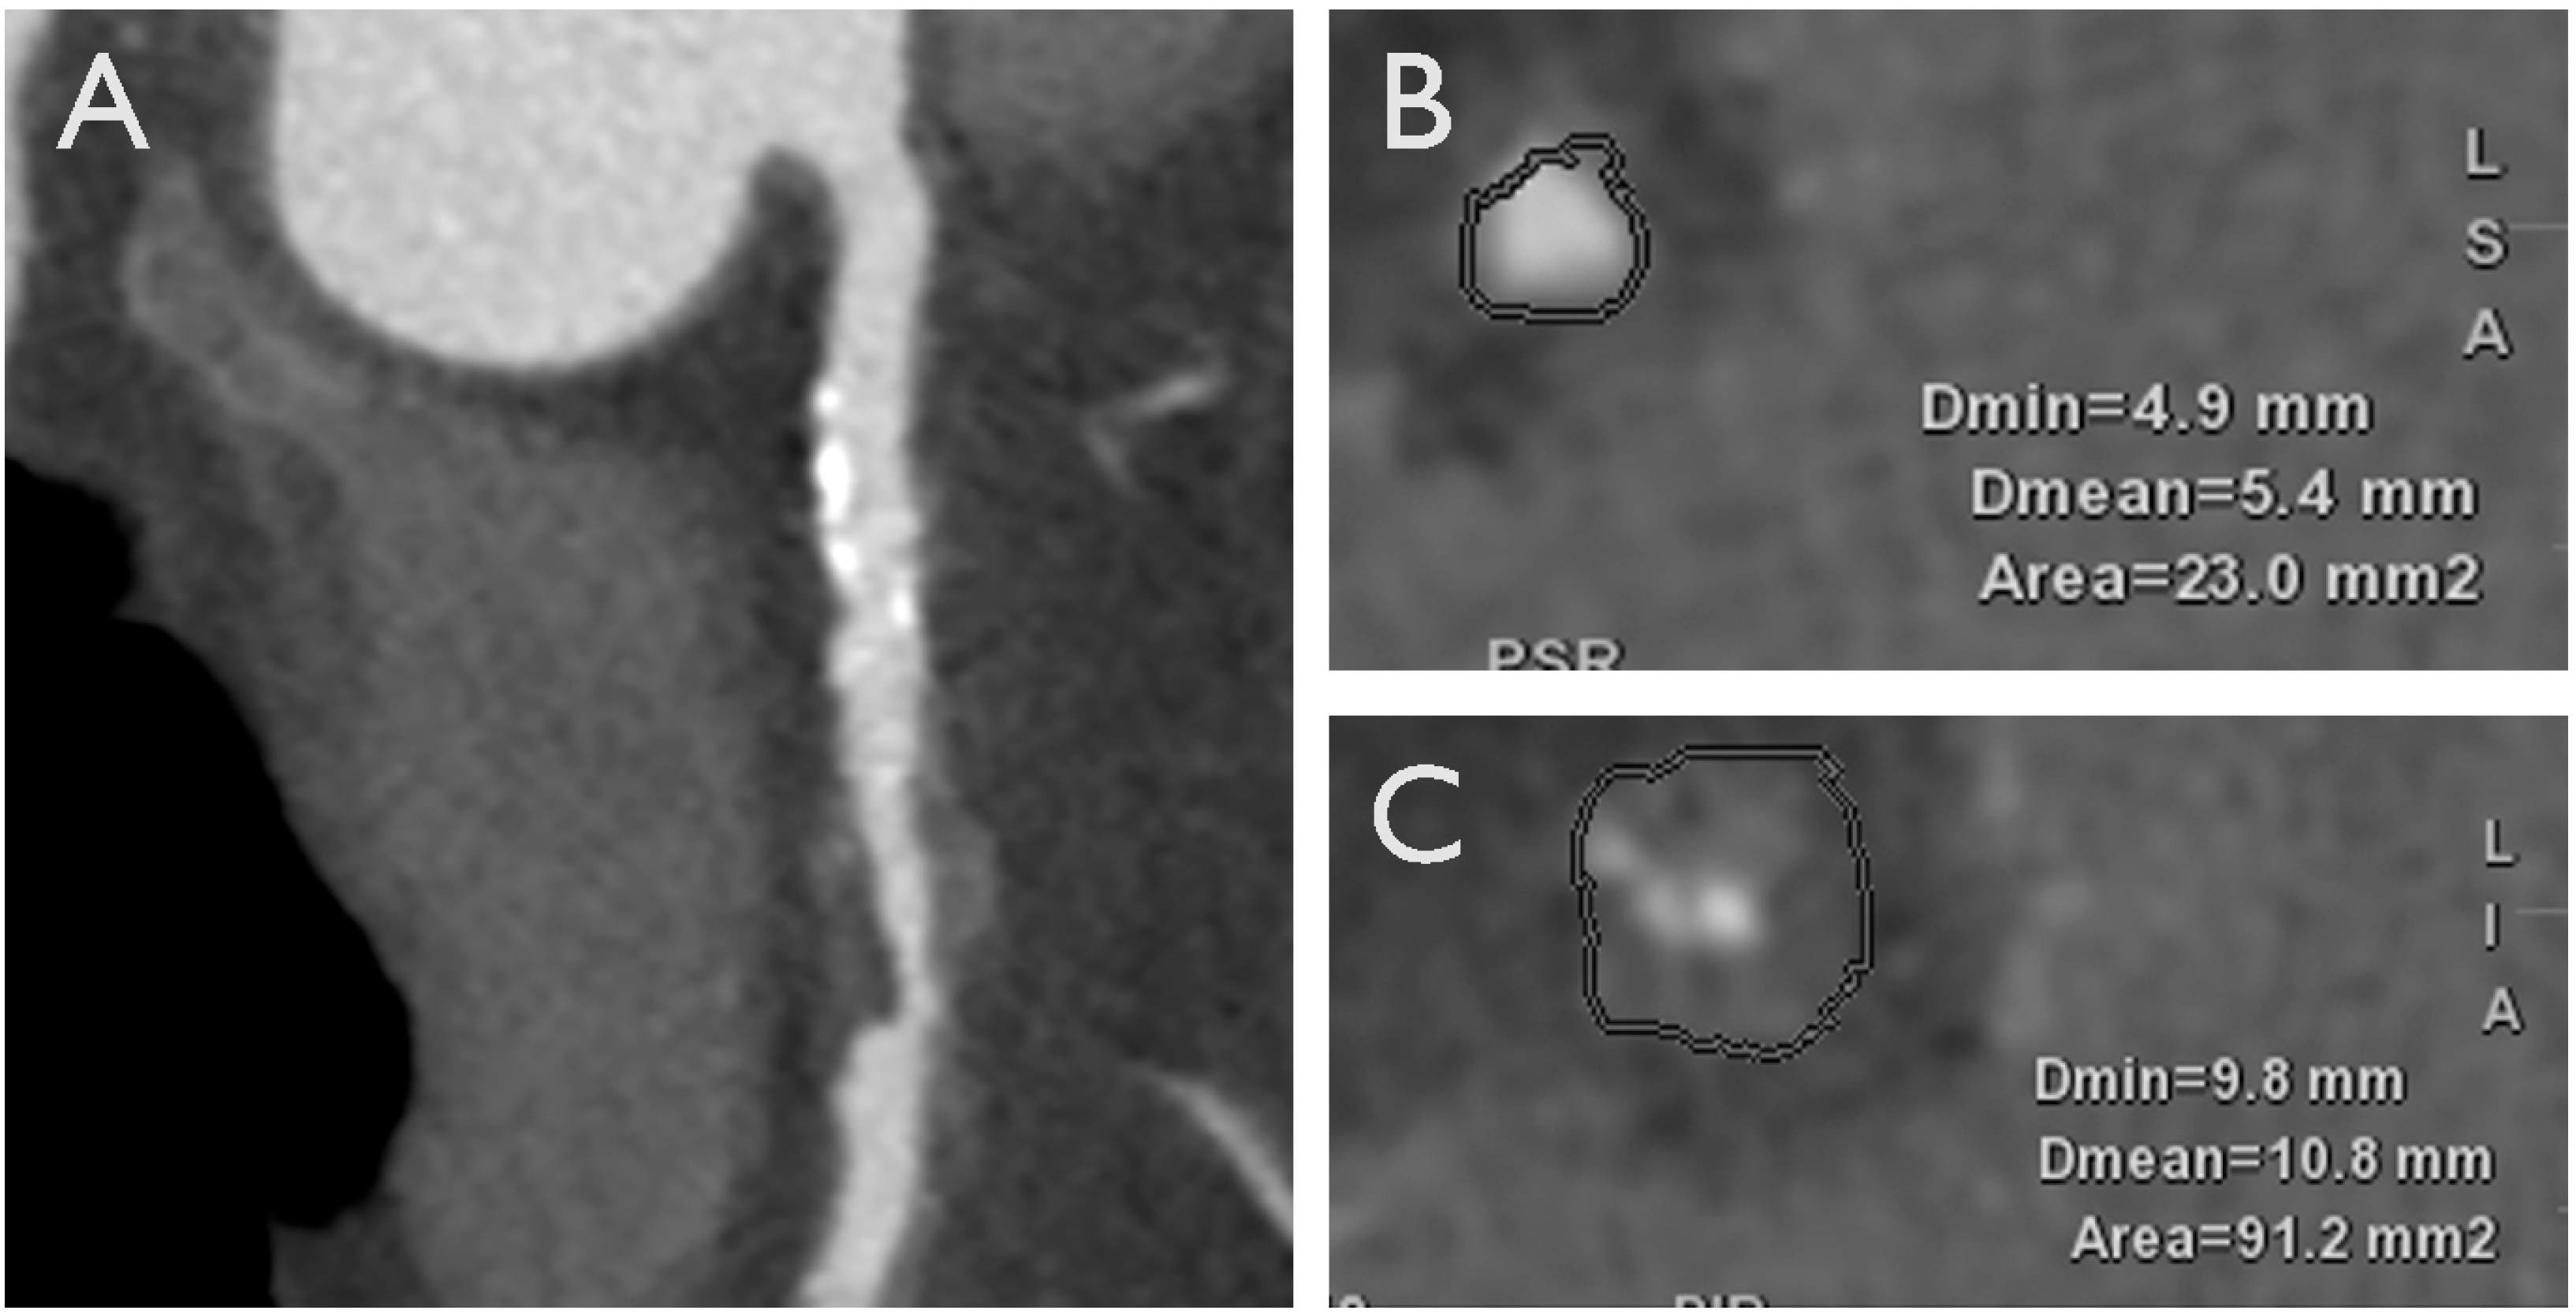

3.1. Adverse Plaque Characteristics

3.2. Adverse Geometric Characteristics

3.3. Adverse Hemodynamic Characteristics